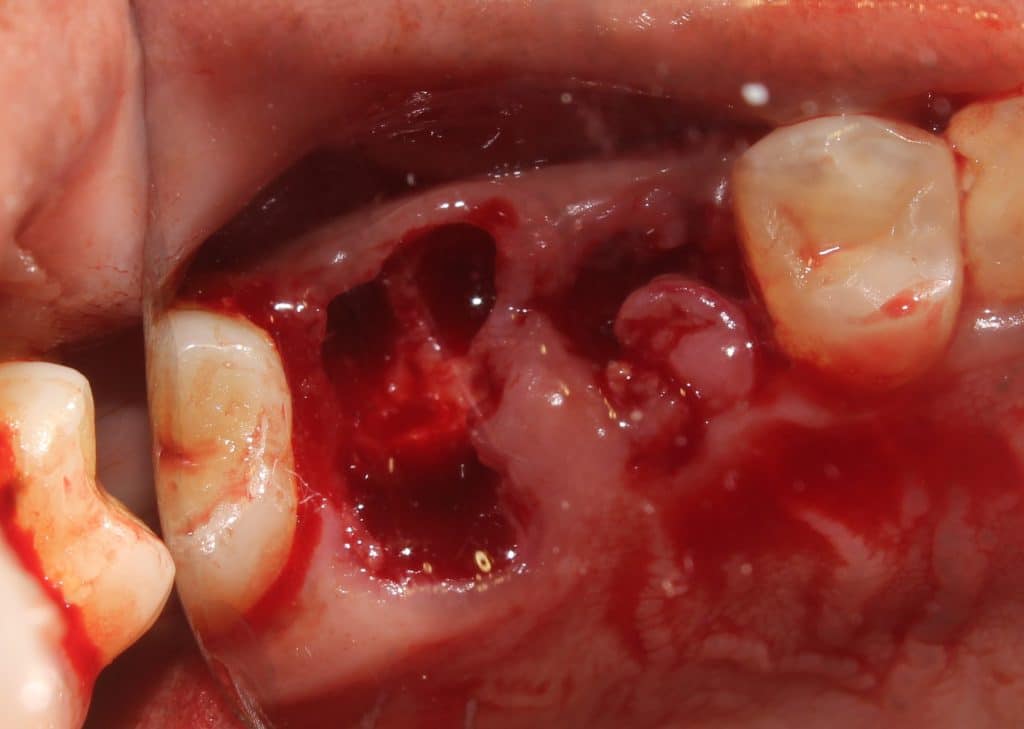

the distal and palatal roots are joined... so sectioning is done..

elevation and root forceps used to remove the distal root..